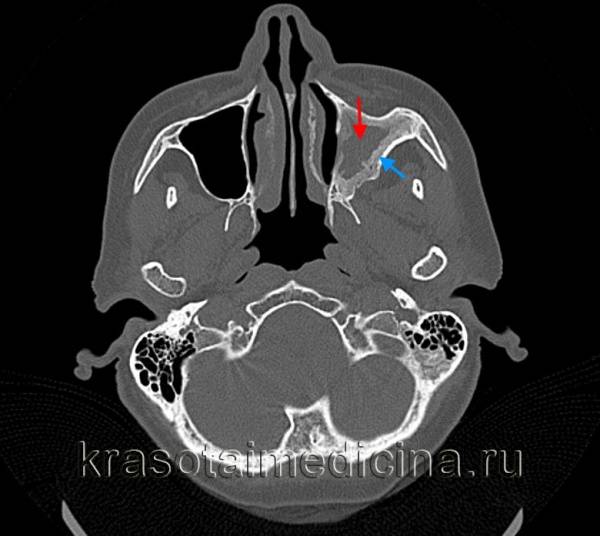

Рентгеновские снимки для визуализации носовой полости лучше делать под общим наркозом, поместив пластинку в открытую ротовую полость, чтобы получить снимок внутренних структур носовой полости.

Поместите рентгеновскую пластинку в ротовую полость. Один угол продвиньте как можно дальше к миндалинам и сделайте снимок в дорсовентральной проекции, в этом случае экспозиция носовых ходов будет наилучшей. Для внутриротовых снимков лучше брать высококачественную безэкранную рентгеновскую пленку либо использовать цифровые технологии

Переднезадняя тангенциальная проекция лучше всего подходит для исследования лобных пазух, кроме того, очень важно получить изображения черепа полностью. Необходимо оценить наличие объемных новообразований или литических изменений в носовых ходах или пазухах

Посмотрите, нет ли асимметрии рентгеновской плотности, признаков лизиса или изменения тонкой спиральной формы носовых раковин, разрывов тонких линий носовой перегородки или затемнений в одной из лобных пазух. Слишком много случаев рака носовой полости остаются незамеченным при первой рентгенографии из-за недостаточной визуализации, поэтому данный метод диагностики крайне редко используется или не используется вообще.

Магнитно-резонансная томография или компьютерная томография носовых ходов и придаточных пазух считаются золотым стандартом визуальной диагностики опухолей носовой полости. Для планирования лечения необходимо определить локализацию новообразования.

Объем новообразования и размер перифокального отека имеют значение для прогноза. Оценить по компьютерной томографии такие параметры, как размер новообразования и отек вокруг опухоли, нельзя.

Технология КТ применяется для компьютеризированного планирования лучевой терапии. Таким образом, если пациент будет получать лучевую терапию, назначение КТ с самого начала может сэкономить время и деньги.